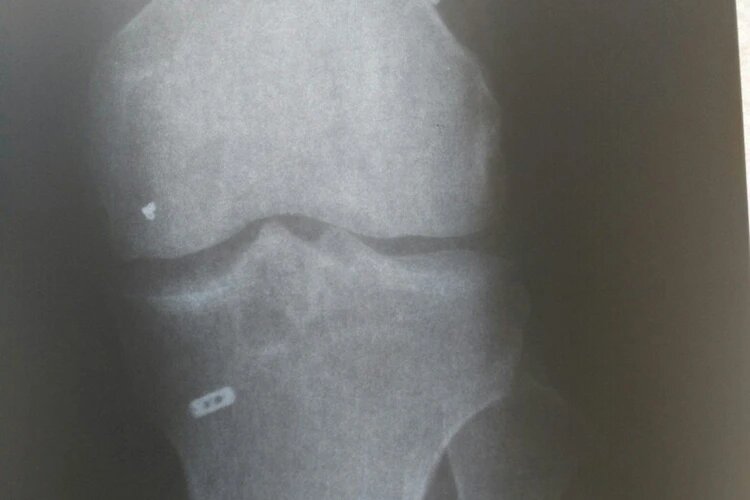

Рентген четко показал расположение, форму и размер инородного тела в колене. Фото: из личного архива героя(ев) публикации.

Мужчина, увидев заключение, не поверил своим глазам. Подумал: «Шутка, что ли, какая-то?» Но рентген окончательно развеял все сомнения. На снимке четко были видны размер, расположение и форма железного кусочка, который 10 месяцев пробыл в ноге мужчины.

- Мне сказали, что это часть хирургического инструмента и что связка не восстановилась. - Голос молодого человека дрожит.